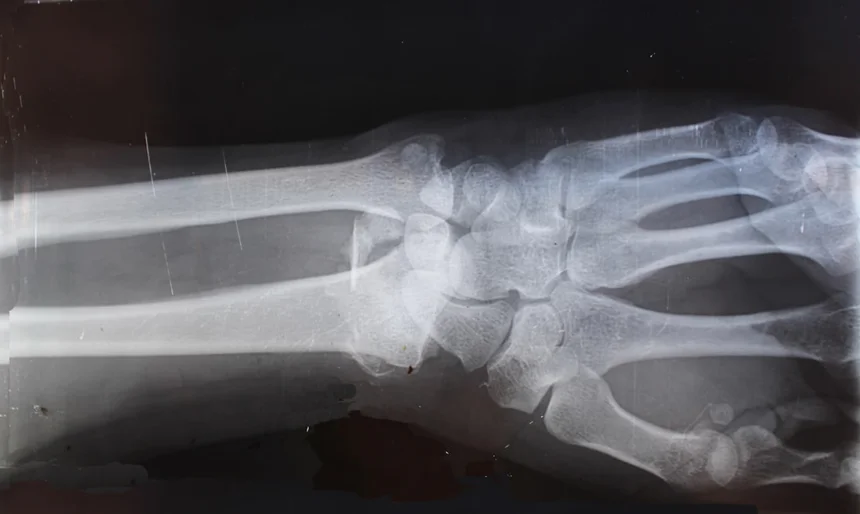

교통사고정형외과의 치료 과정은 초기 진단을 포함하여, 점진적인 회복 과정으로 이어집니다. 먼저, 의료진은 기본적인 신체 검사를 진행한 후, 필요시 X-ray나 MRI 검사를 통해 부상의 상세 내용을 파악합니다. 그런 다음, 환자의 상태에 맞춘 치료 계획이 수립되며, 이는 환자의 회복에 중요한 요소로 작용합니다. 이제 치료 과정에 대해 더 살펴보는 시간을 가져보겠습니다.

| 진단 | X-ray / MRI 등을 통해 부상 파악 |